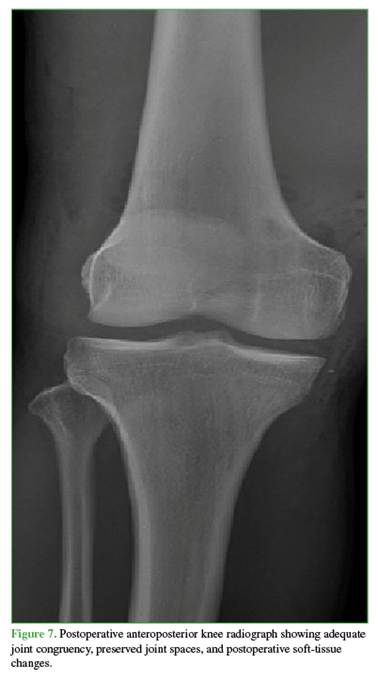

A longitudinal medial approach was carried out, and the extensor mechanism was released to evaluate the articular surface of the patella and increase exposure. The medial femoral condyle was found to be completely denuded. Careful flap dissections were performed to improve visualization despite the everted patella. Through valgus maneuvers, the relevant structures were identified and localized. Attempts were made to remove the interposed meniscus, medial retinaculum, and capsule using levering techniques with different instruments, but this was unsuccessful due to tension within these structures despite reduction maneuvers. Therefore, the capsule and the patellofemoral ligament were sectioned to release the femorotibial and intercondylar space, achieving clinical reduction and congruency of the knee. Copious irrigation with saline solution was performed, followed by capsular repair and suturing of the medial patellofemoral ligament and medial retinaculum. Stability was reassessed, and the knee did not redislocate with deep flexion or extension. No chondral lesions were observed in the patella or trochlea. The medial meniscus was found to be impinged but without body or root tears; therefore, no further management was required. An articulated knee brace was applied, postoperative radiographs were obtained (Figure 7), and delayed ligament reconstruction was scheduled for 3 weeks later. During that procedure, the anterior cruciate ligament was reconstructed with an allograft; the posterior cruciate ligament was reconstructed using a single-bundle allograft technique; and the posteromedial corner was reconstructed using the LaPrade technique. At 4-week follow-up, knee range of motion was 10° to 90° of flexion. The patient continues with physical therapy.